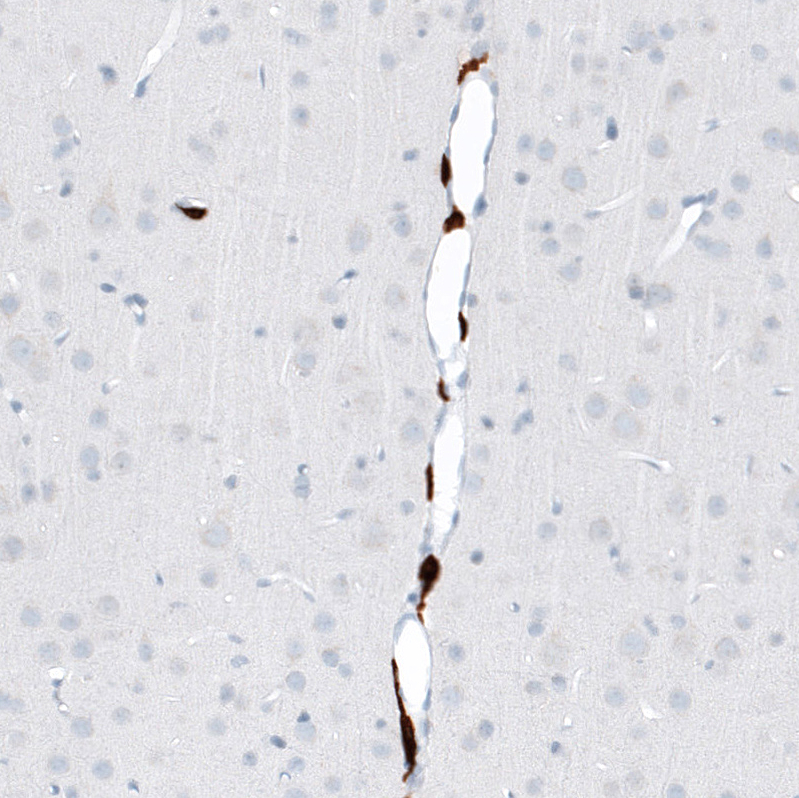

Immunohistochemistry analysis in human cerebral cortex and skeletal muscle tissues using AMAb91646 antibody. Corresponding CD163 RNA-seq data are presented for the same tissues.